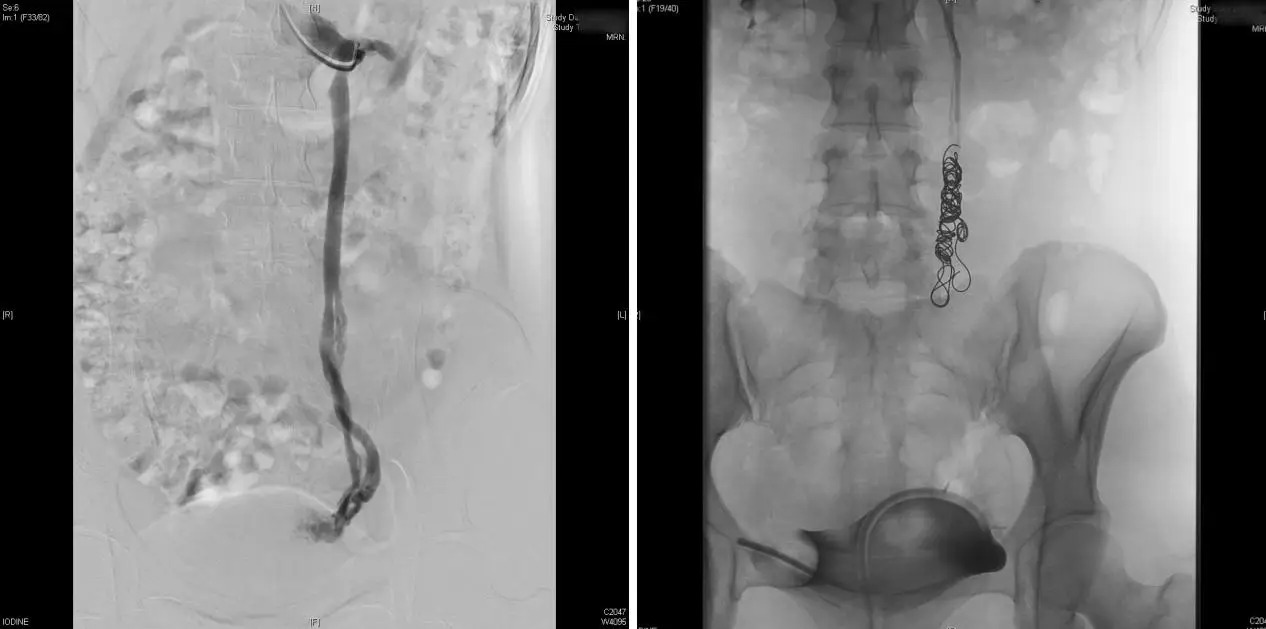

Sau khi tìm đúng "hang ổ" của bệnh, chị Chen Fan được thực hiện thủ thuật thuyên tắc tĩnh mạch buồng trứng.

Bác sĩ Zhao giải thích: "Đây là kỹ thuật can thiệp mạch máu xâm lấn tối thiểu. Bác sĩ chỉ cần chọc một lỗ nhỏ ở tĩnh mạch cánh tay để đưa thiết bị vào chặn các mạch máu bị giãn nở".